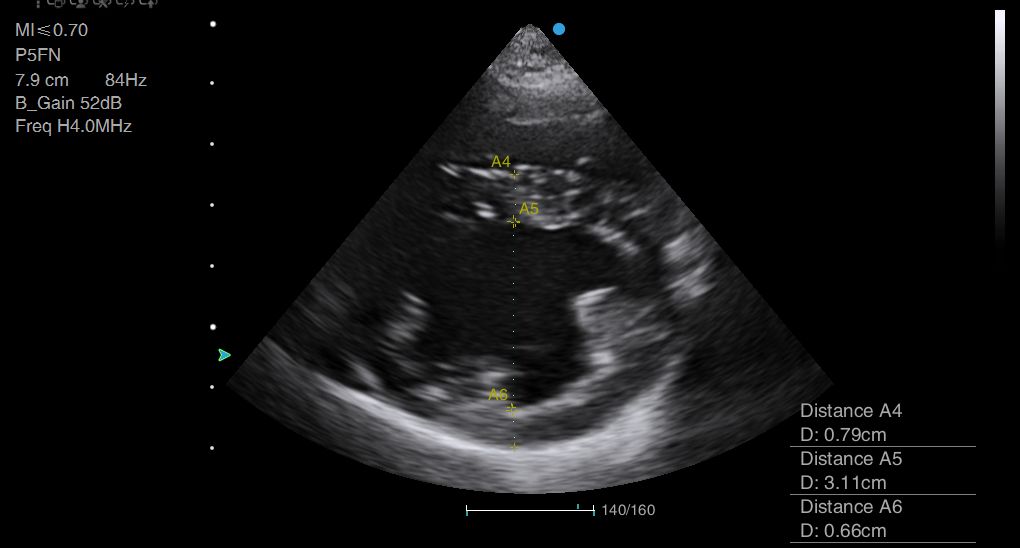

Above: Wall thickness and cavity diameter measurements can be time-consuming to perform, and could be very easily automated.